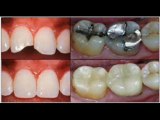

Dentin (American English) or dentine (UK English)(Latin: substantia eburnea) is a calcified tissue of the body, and along with enamel, cementum, and pulp is one of the four major components of teeth. It is usuallly covered by enamel on the crown and cementum on the root and surrounds the entire pulp. By weight, 70% of dentin consists of the mineral hydroxylapatite, 20% is organic material, and 10% is water.[1] Yellow in appearance, it greatly affects the color of a tooth due to the translucency of enamel. Dentin, which is less mineralized and less brittle than enamel, is necessary for the support of enamel.[2] Dentin rates approximately 3 on the Mohs scale of mineral hardness.[3]